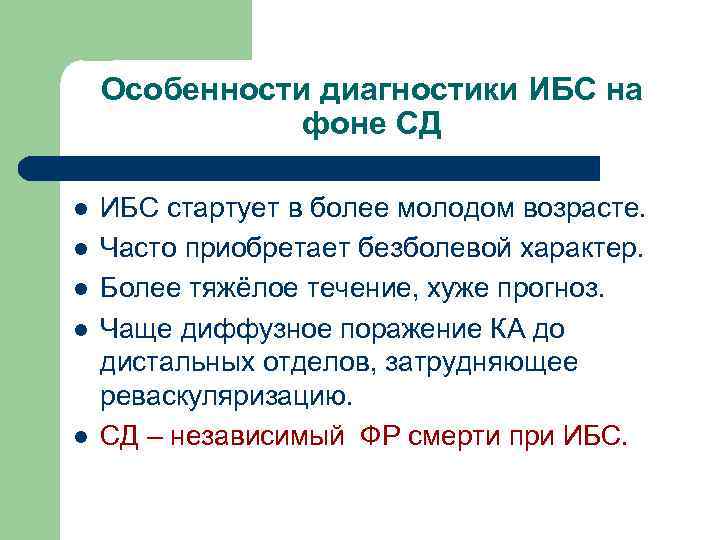

Особенности диагностики ИБС на фоне СД l l l ИБС стартует в более молодом возрасте. Часто приобретает безболевой характер. Более тяжёлое течение, хуже прогноз. Чаще диффузное поражение КА до дистальных отделов, затрудняющее реваскуляризацию. СД – независимый ФР смерти при ИБС.